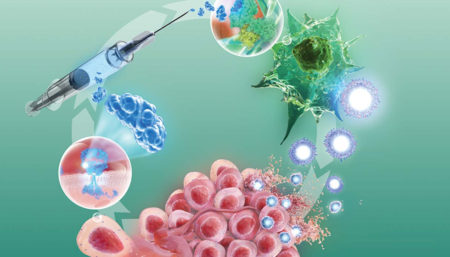

Researchers a Step Closer To a Cure For HIV

Cancer News

Why Cancer Immunotherapies don’t Work for Everyone